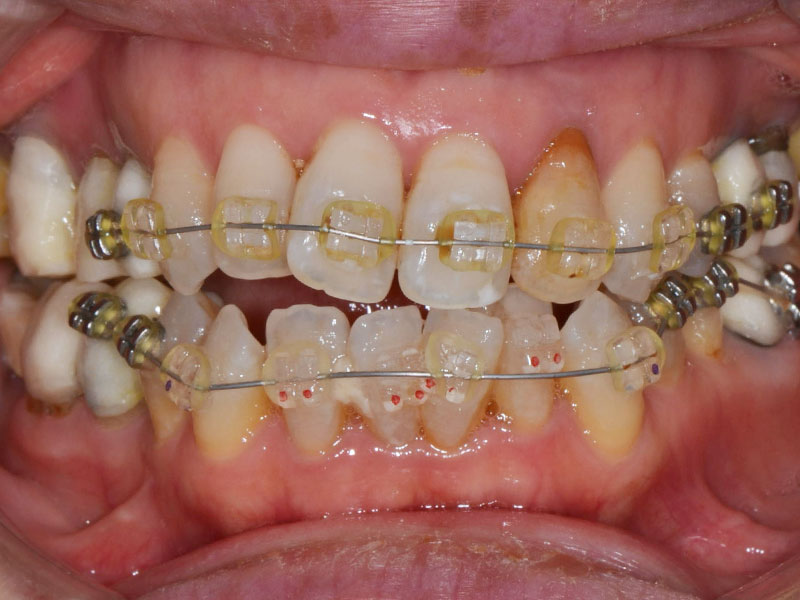

噛み合わせ治療の実際は上に示したように、咬合挙上をする(噛み合わせの高さをあげる)ことがほとんどです。咬合挙上とともに咬合治療を行った症例です。

初診時

矯正治療を含めて咬合挙上した症例

| 年齢・性別 | 50代・女性 |

| 主訴 | 顎が痛い、疲れる。 |

| 治療期間 | 約2.5年 |

| 費用 | 総額:140万円+保険費用 |

① 咬合基本治療:3ヶ月

マウスピース(2つ作成)にて正しい噛み合わせの位置の確認、習慣化。診査診断。

② 咬合口腔内反映:1ヶ月

口腔内反映とは、マウスピースにて得た正しい噛み合わせはマウスピースを装着した状態でのものであり、マウスピースを外すと元の悪い噛み合わせに戻ってしまいます。

マウスピースを外しても正しい位置で噛み合うように仮歯、仮の詰め物にて噛み合わせを調整します。

この作業を口腔内反映と呼びます。

③ 矯正治療:1.5年